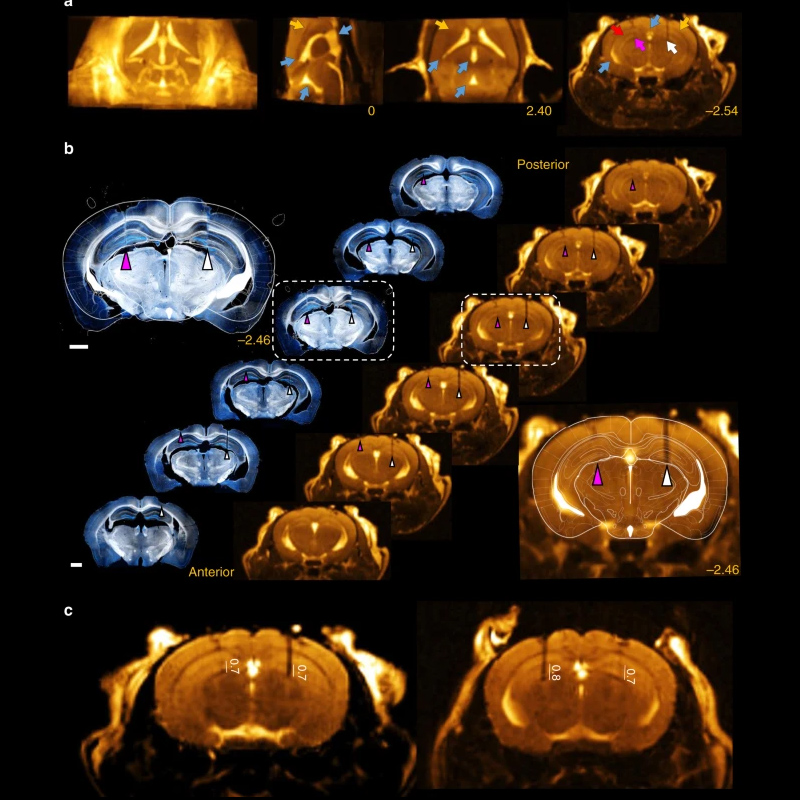

用于光遗传学探针植入的快速BSSFP序列

该方法结合了微CT扫描提供的高分辨率骨标志信息与MRI的软组织对比度,能够在大鼠活体中精确定位电极和光纤。

〉动物模型:Wistar大鼠

〉序列: 3D bSSFP,

磁场强度:3T,

平面内分辨率:100µm,

重复时间(TR):25ms,

回波时间(TE):2.7ms

〉线圈: 72mm Tx/Rx体积线圈,用于传输和 20毫米柔性光遗传表面线圈,用于信号接收